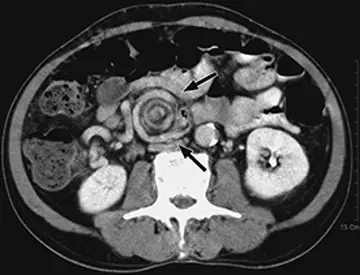

ایلئوس شبه مکونیوم

یک خانم 19‌ساله با دیابت ملیتوس نوع1 و مشکوک به فیبروز کیستیک با سابقه‌ی یک روزه‌ی درد حاد شکم مراجعه نمود.